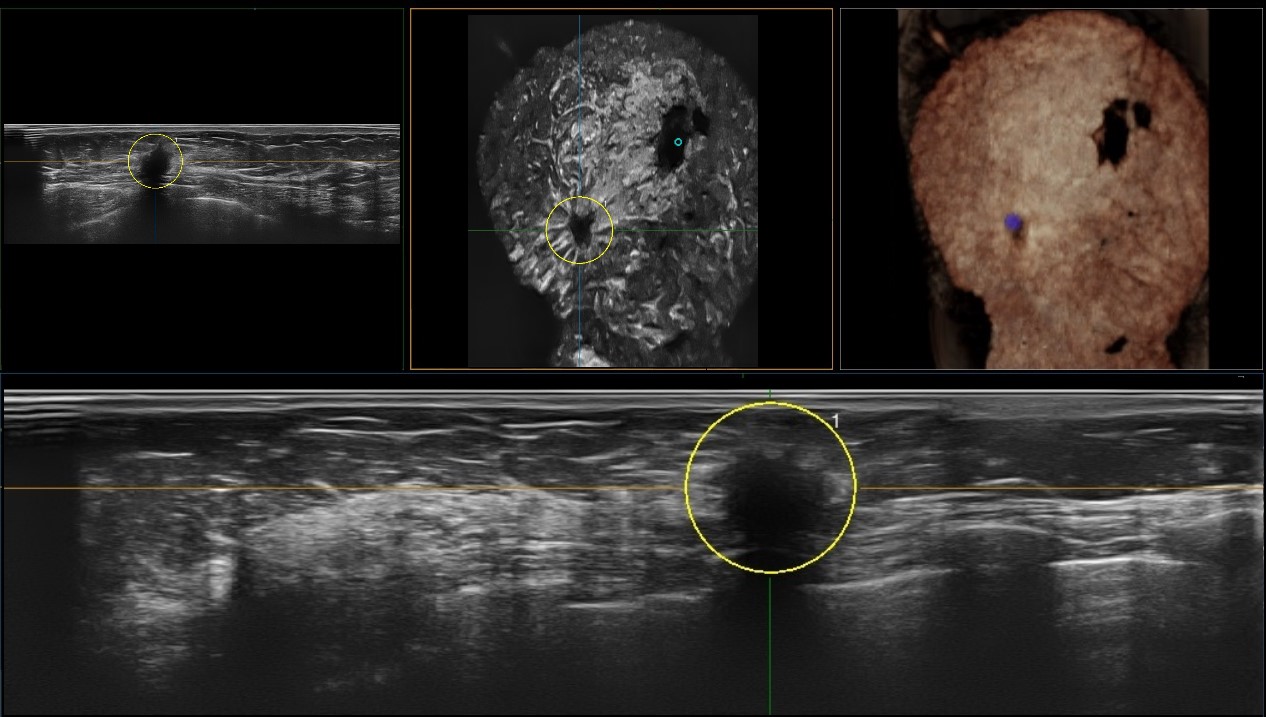

Full Volume Imaging and Coronal Section with High Clinical Value

IBUS acquires volume data from multiple sections to provide abundant information. The coronal section intuitively shows the anatomical information of breast tissue in a supine position during operation, which helps surgeon to perform more accurate surgical planning.

Intelligent Breast Solutions on the Workstation

Automatic lesion detection powered by AI identifies suspected area and traces the lesion from multiple sections. Quantitative coordinate position and graphic indication will be displayed for precise lesion localization.

Lesion stereo images are generated from volume data rendering. It provides intuitive and detailed information for better observation and lesion localization.

Lesion correlation correlates the information obtained from different scanning positions and sections to avoid misdiagnosis.